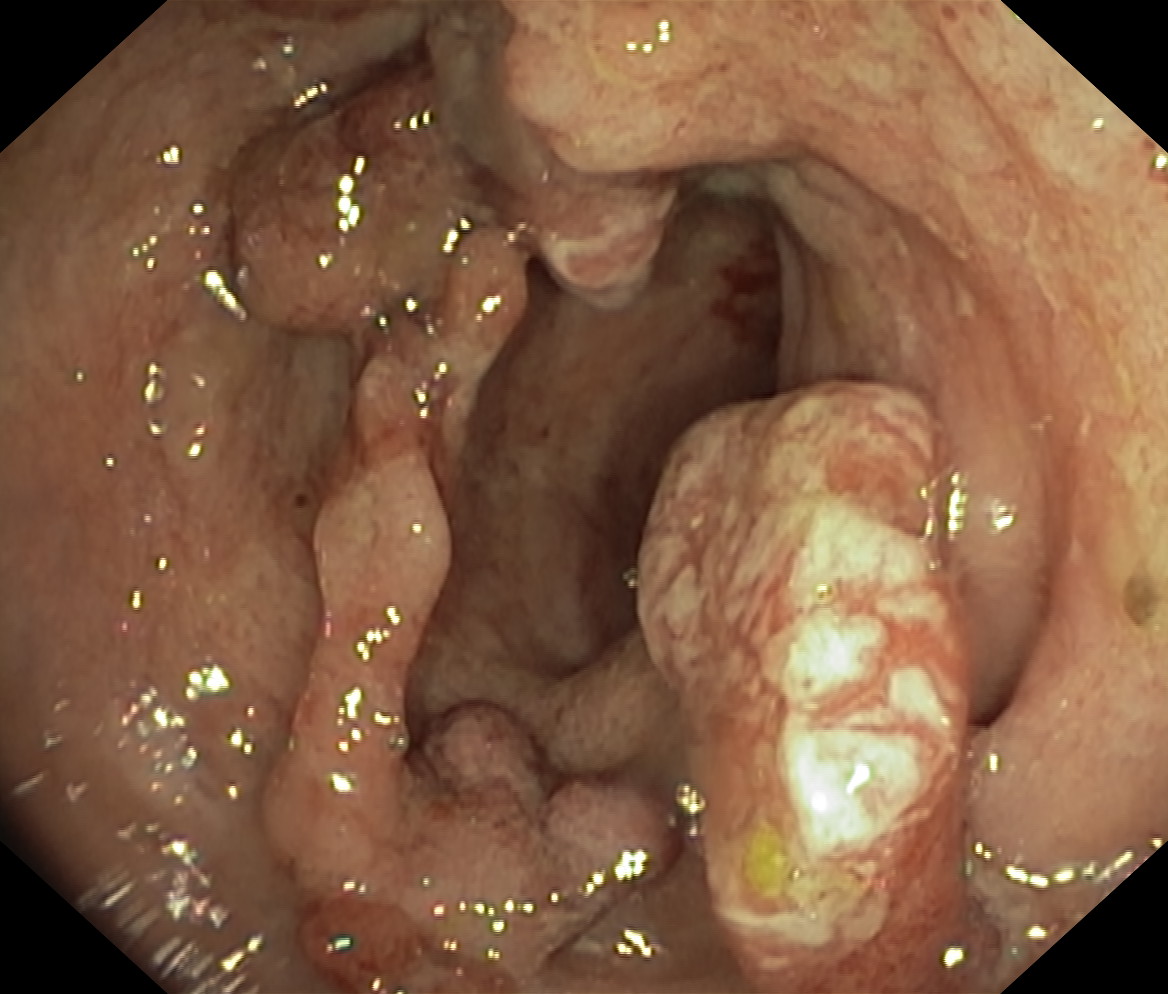

Obrazy endoskopowe

Nowotwory przewodu pokarmowego